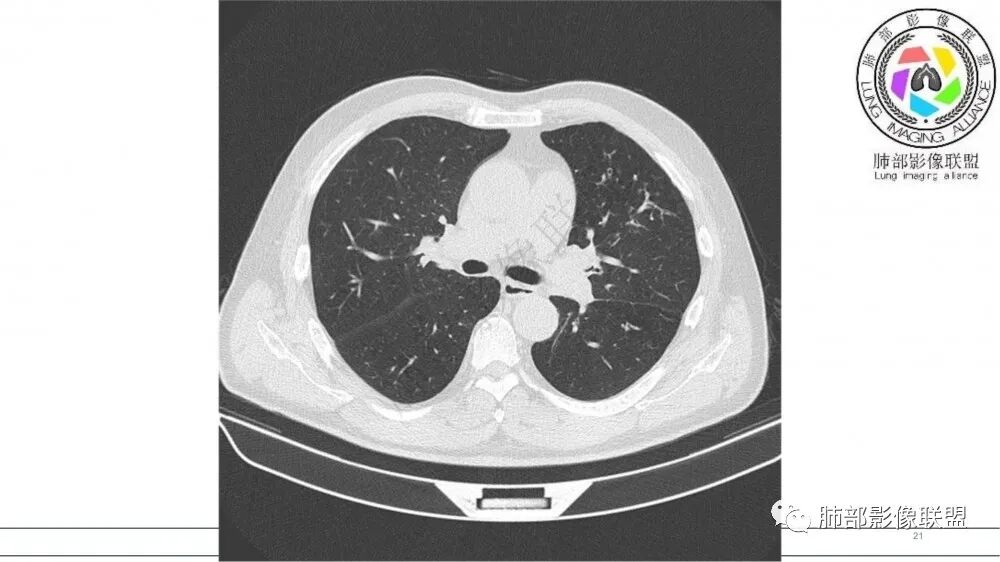

猜个鳞,沿支气管塑型生长,周围小花小草,肺门及纵隔淋巴结增大,吸烟老年男。鉴别TB

病灶有强化,粘液栓不考虑。沿着支气管生长,远端小花小草,恶性首先考虑。鉴别结核

老年男性,肺气肿,吸烟史,左肺上支气管腔内铸型高密度影,呈指套状,远端多发树芽,增强不均匀强化,考虑鳞癌,鉴别小细胞癌

70岁男,吸烟史,左肺上叶不规则肿块,轻度强化,前段支气管增厚,周围可见阻塞性小花小草,考虑鳞癌

小花小草,支气管阻塞,考虑鳞癌,鉴别腺癌,结核,及淋巴瘤

老年吸烟男,左肺上叶支气管堵塞,远端小花小草,纵隔未见肿大淋巴结,考虑鳞癌,建议进一步支气管镜检查

指套征,扩张支气管内软组织强化,远侧肺野阻塞性炎,纵隔、左肺门肿大淋巴结;老年男性,吸烟,考虑鳞癌,鉴别小

指套征:是影像征象,胸部平片表现为手指状密度增高影,以肺门为中心呈放射状分布,CT显示扩张支气管内低密度黏液栓形成或实性病变,呈管状、树枝状或卵圆形密度增高影;支气管扩张伴近端梗阻时,扩张支气管内部黏液分泌物不能排出而形成。可以伴随远端空气潴留征、阻塞性炎症。

研究报道,中心型 SCLC 经 CT 扫描后通常支气管表现为鼠尾样狭窄,肺门或纵隔肿块明显,由于肿块沿管壁生长表现为顺延支气管形态的不规则形状。病灶相对特征性影像学表现比如鸭蹼状、腊肠状、葫芦状及葡萄状改变,可以出现血管包埋,很少有空洞、空泡,较少引发肺不张,阻塞性炎症成都较轻。与一般肺癌比较,恶性程度高,侵袭力强、病灶很小就容易远处转移!Herzberg 等[19]研究指出,20%以上 SCLC 倍增时间短,预后不良。